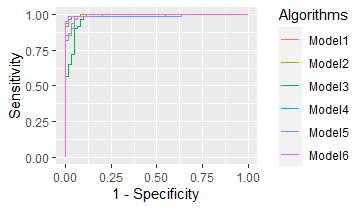

3.2 Performance: Proposed Models

This subsection we present the experimental results. A brief summary of comparison of conventional methods literature and the proposed method is presented in Table 3. A detailed report of the proposed methodology is presented in Table 4. We also plot the AUC values for the proposed models in Figure 9.

The report in Table 3 shows results of previous work on this data set. Minaee et al. (2020) [20] used a 50-layer Convolutional Neural Network, ResNet50, and delivered a value of AUC at 99%. Their work also proposed SqueezeNet that delivered an even higher performance at 99.2% [20]. This near-perfect performance is largely due to the design of the convolutional layers and fine tuning. Their work show that modern day AI technology such as deep Convolutional Neural Network can provide initial screening of COVID-19 diseased patients with a single scan of an image which could provide reduce workload for radiologists in practice. However, the number of parameters still far exceeds what humans can interpret. Moreover, it is unclear how these conventional methodologies can satisfy the three dimensions (, , and ) of the definition of interpretable measures introduced in §1 of this paper.

We read the experimental results of the proposed model in the following order. As stated in section §3.3, the proposed architecture can be designed as deep or wide as the user desires. All models start with input images with dimensions 128 by 128. In other words, the input data has pixels. For simplicity of notation, let us denote to be the set of parameters of starting point of 6, window size of 2 by 2, and a stride level of 2. Let us further denote to be the collection of parameters of starting point of 1, window size of 2 by 2, and a stride level of 2.

Model 1. This model starts with input images that are sized 128 by 128. Using the parameter in set , we create the first Interaction-based Convolutional Layer (namely 1st Conv. in Table 4). This new matrix has dimension . These 3,721 variables are used directly to create output layer with 2 units (assuming using softmax as loss function). Therefore, the total number of parameters for the network architecture parameters. The test set performance, measured by AUC, is 98.5% for Model 1.

Model 2 - 6. We also provided more updated versions of Model 1. Please see appendix. 5.7

| Proposed Work | 1st Conv. | 2nd Conv. | Hidden | Output Layer | Num. of Param. | AUC |

| Model 1 | None | None | 2 | 7,442 | 98.5% | |

| Model 2 | None | 1L(64 units) | 2 | 238,272 | 99.7% | |

| Model 3 | None | 2 | 1,800 | 97.0% | ||

| Model 4 | 1L(64 units) | 2 | 57,728 | 99.6% | ||

| Model 5 | None | None | 2 | 9,242 | 98.3% | |

| Model 6 | None | 1L(64 units) | 2 | 295,872 | 99.8% | |

| Remark | : | : | ||||

| Starting Point = 6 | Starting Point = 1 | |||||

| Window Size: 2 by 2, | Window Size: 2 by 2, | |||||

| Stride = 2, | Stride = 2, | |||||

| Output: 61 by 61 | Output: 30 by 30 |

Model 2. This model builds up the architecture of Model 1. The only difference is that there is one hidden layer with 64 units (or neurons). We fully connect each variable in 1st Conv. layer with each neurons in the hidden layer and afterwards we fully connect the hidden layer with the output layer. This means that from 1st Conv. Layer to the hidden layer there are parameters. From the hidden layer of 64 neurons to output layer with 2 units, there are parameters. This means in total there are parameters. The performance for this architecture is 99.7%. The design of this one hidden layer with 64 units reduced the error rate from 1.5% in Model 1 to 0.3% in Model 2, which is 80% error reduction.

Model 3. This model aims to build two Interaction-based Convolutional Layer. The 1st Conv. Layer uses the set of parameters in and the 2nd Conv. Layer uses the set of parameters in . From the 1st Conv. Layer in Model 1, we are left with variables. Using the parameters in , we have new matrix with size variables. These 900 variables can be input layer and we can directly pass these 900 variables into the output layer for making predictions. In other words, the output layer has parameters. The test set AUC value is 97.0%.

Model 4. This model is the deepest amongst all six models. More specifically, Model 4 has two Interaction-based Convolutional Layers and one hidden layer. From the 2nd Conv. Layer in Model 3, we are left with 900 variables. The architecture has one hidden layer with 64 units. The 900 variables are fully connected with the hidden layer which create variables. From the hidden layer with 64 units to output layer with 2 units, there are parameters. In total, there are parameters. The prediction performance is 99.6% on test set.

Model 5. Both Model 5 and Model 6 build wider convolutional layers instead of aiming for depth. Model 5 has a concatenated of features from both convolutional layers. This means the architecture takes the 7,442 variables from the 1st Conv. Layer and 900 variables from the 2nd Conv. Layer from previous models together as one large convolutional layer. In other words, Model 5 has 1st Conv. Layer of variables. These 4,621 variables can be used directly to be fed into the output layer with 2 units. In total, this architecture creates parameters with test set performance to be 98.3%.

Model 6. The last model, Model 6, is just as wide as the previous model, Model 5. Model 6 also has a first convolutional layer that is concatenation of features. It has variables. In addition to Model 5, it has one hidden layer with 64 units. We fully connect the convolutional layer of 4,621 variables with the hidden layer of 64 variables. This gives us parameters. The hidden layer with 64 units are then fully connected with the output layer which gives us parameters. In total, the model has parameters. This model has the highest AUC value on test set, i.e. 99.8%.